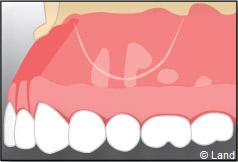

Une anesthésie et une incision semi lunaire sont réalisées et le lambeau de gencive est récliné.